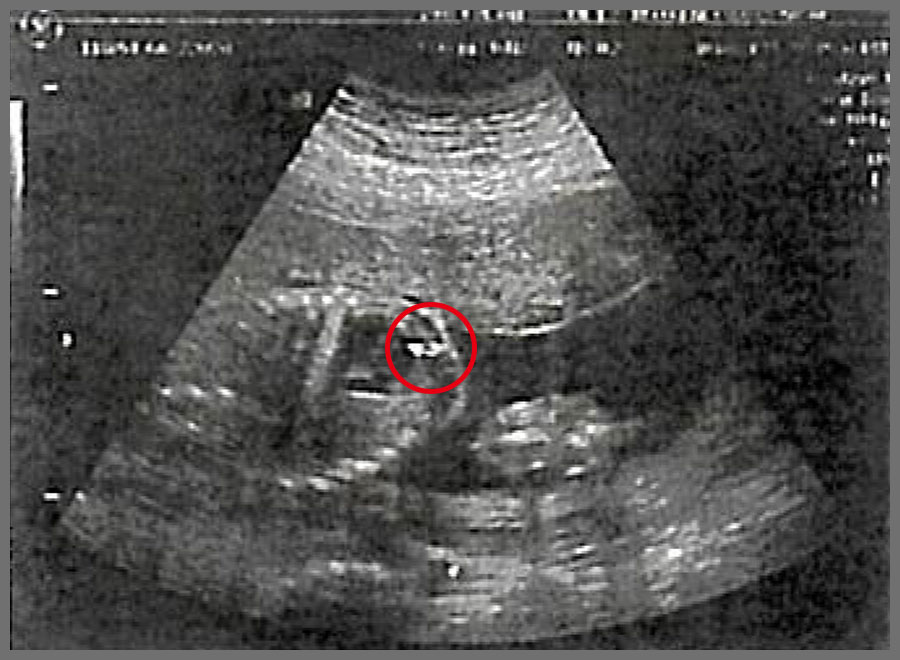

林姿君懷孕22周產檢時,胎兒心臟發育鈣化,產生兩個白點

在第28週到醫院檢查,當天超音波大概照了約30分鐘,等於超音波檢查又完整做了一遍,當天檢驗師幫胎兒全身的每一個地方都拍得很澈底,尤其是心臟的部分,她看了很久,檢驗師才跟我們說,胎兒心臟的白點並沒有看到,心臟的白點確定已經消失了,我們當下跟檢驗師說這是因為有尊貴的金剛上師 仁欽多吉仁波切的加持,胎兒才能從22週拍到心臟有2個白點,到28週心臟白點完全消失,真的太不可思議了,這一切都要感恩尊貴的金剛上師 仁欽多吉仁波切。